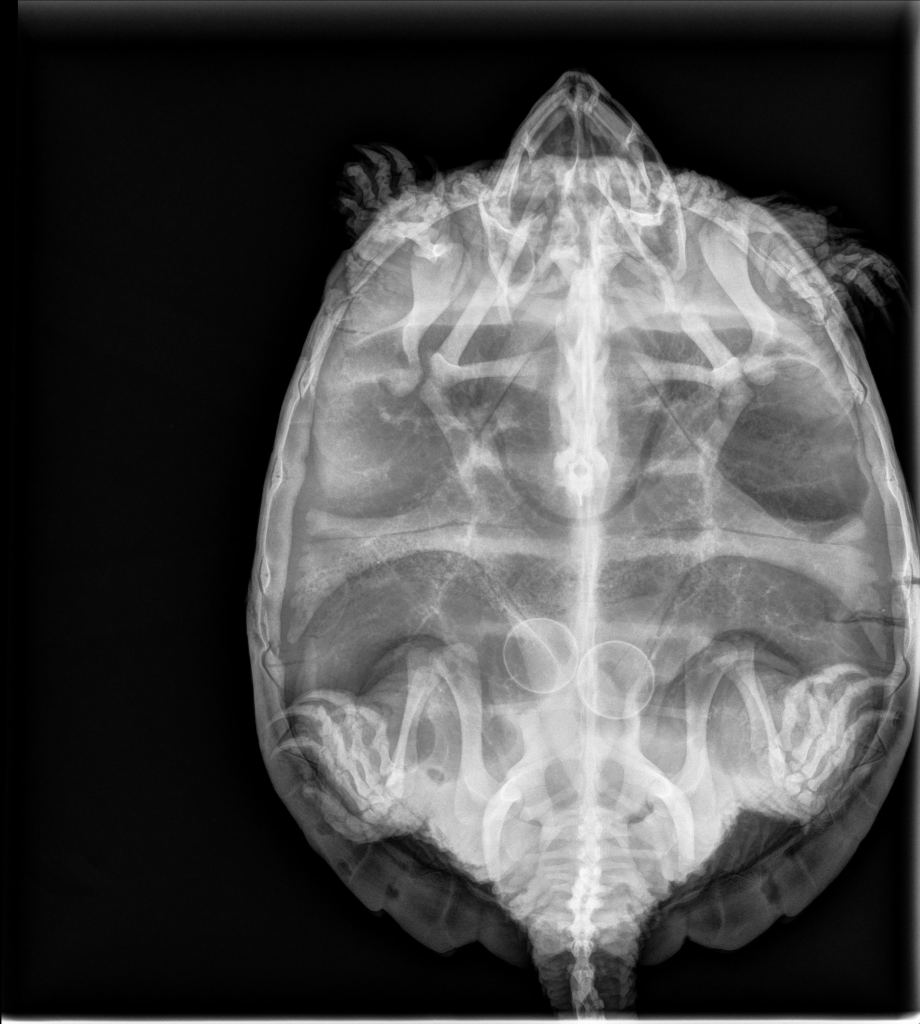

Freyja was with me for a little over a year before she was healed enough to go back to the wild. During that year, she attacked and broke three different filters. She went from hissing and trying to bite when I approached to swimming over and splashing to ask for food, which she eventually learned to take gently from my tongs or delicately grab from the surface of the water. When she was finally ready to go, I took her to the vet to get an x-ray, as a final check that she hadn’t developed any new eggs in the time she had been in rehab, or, worse, still had some stuck from her initial intake. I don’t want to release gravid turtles, because they may not lay the eggs in the wild. The timing and hormonal cues and seasonal cues have all been messed up from being in rehab for so long. And once they’re out there, there’s nobody to check up on them.

Lo and behold, she had two eggs stuck inside her. Now, it is possible to palpate in front of the hind legs to tell if a turtle is gravid, but it’s inexact. If she has a whole clutch, you can tell she’s gravid. But if she has only a couple eggs in a weird spot, it’s easy to miss or to not be sure that’s what it is. Hence, the x-ray. This presents a new problem for me, because the vet I would normally go to for help inducing egg-laying wasn’t taking wildlife anymore this year, and none of the six other vets I talked to would either induce her themselves, provide the medications for me to induce her, or consider any other measures (such as surgery) if she didn’t lay them. Every vet has their own limitations on what they feel they can handle, and many who don’t see turtles or wildlife all the time understandably don’t want to jump in on a complicated case. So, I went to my fellow rehabber who initially referred this patient to me, and she gave me medication to induce her.